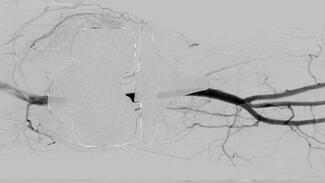

Two cases are presented of patients who had minimal intraoperative blood loss secondary to IR placement of intra-arterial occlusion balloons prior to evacuation of cervical ectopic pregnancy.